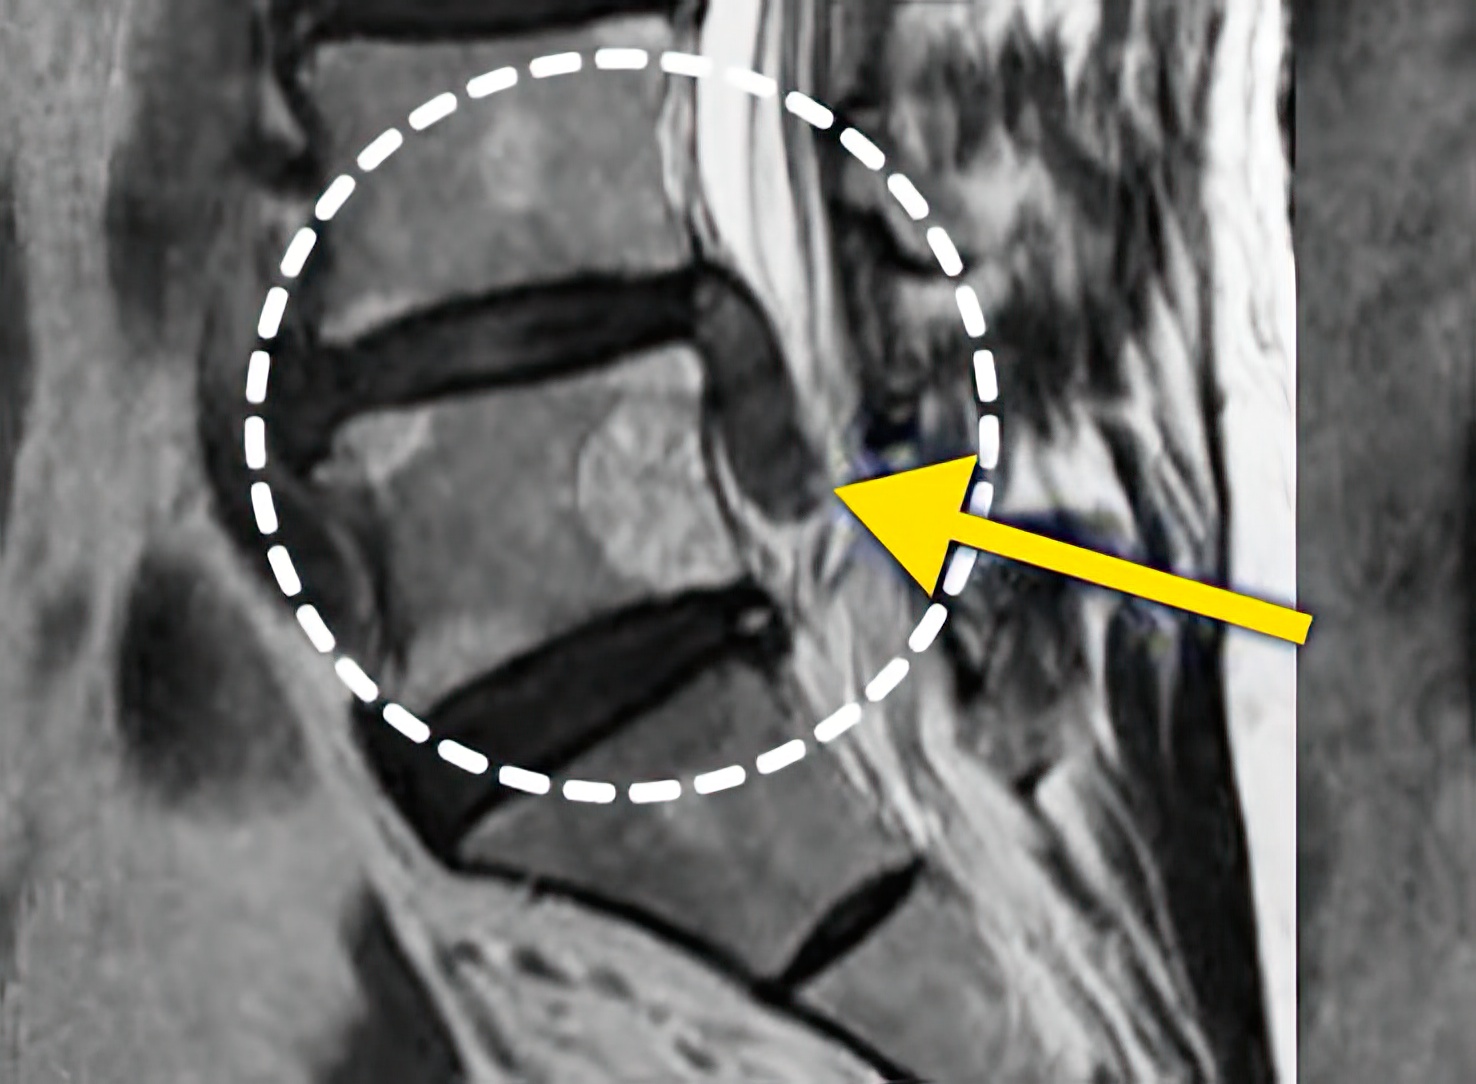

자생 비수술 한방통합치료 후

터진디스크가 흡수된 모습

After

터진디스크 한방통합치료 후

비수술 치료만으로

터진 디스크 흡수

튀어나온 디스크 대비,

터진 디스크 치료 효과 우수

디스크 흘러내린 정도가

심할수록 흡수 가능성 증가

치료 후 장기추적관찰 결과,

환자 90% 이상 치료 만족